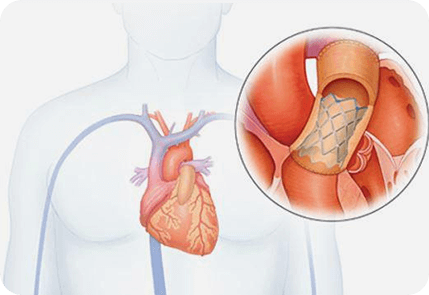

介入治疗

目前,介入治疗已成为结构性心脏病最重要的发展方向。

就结构性心脏病介入治疗而言,主要包括以下技术:

先天性心脏病的经导管封堵;

传统的经导管瓣膜治疗术:

经皮二尖瓣球囊扩张(percutaneous balloon mitral valvuloplasty,PBMV)

经皮肺动脉瓣球囊扩张(percutaneous balloon pulmonary valvuloplasty,PBPV)

经皮主动脉瓣球囊扩张(percutaneous balloon aortic valvuloplasty,PBAV),

经导管瓣周漏封堵(Paravalvular Leak closure)等。